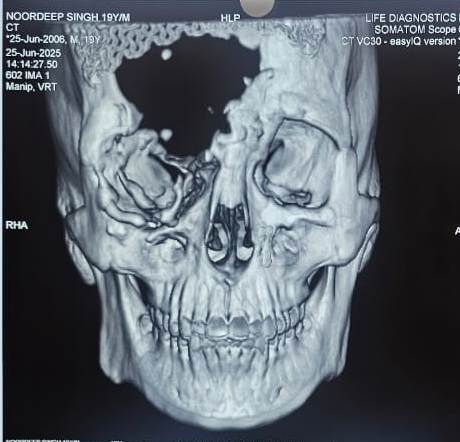

Pre-surgery condition of the patient with severe forehead trauma.

A 19-year-old boy from Nabha, District Patiala, underwent a remarkable surgery at Deep Hospital, Ludhiana, where a 3D printed forehead bone was used to reconstruct his face after a life-threatening cattle gore injury. The patient, who had already endured over six major surgeries, finally saw hope and healing through this innovative procedure.

Dr. Ashish Gupta, Director of the Department of Plastic Surgery, explained, “3D printing is a boon for patients with complex defects that are difficult to correct using traditional methods.” By using CT scans of the patient's skull, doctors created a digital model and generated a mirror image of the unaffected side to restore facial symmetry. This custom bone was then printed using advanced 3D printing technology and surgically implanted to achieve a natural-looking result.